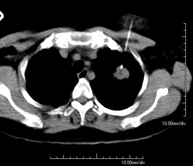

- Chest CT

Diagnostic test that provides high definition anatomical images of the chest (lungs, heart, mediastinum, great vessels, rib cage, etc.) using CT (Computed Tomography) equipment. These images are then examined on a workstation that allows bidimensional reconstructions in different planes of space and also 3D reconstructions (volumetric). Some studies require the use of an iodinated contrast agent to improve image definition.